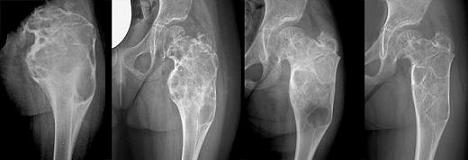

Lesione espansiva osteolitica del femore prossimale sinistro riferibile a cisti aneurismatica in bambina di 4 anni: radiografia (a sinistra) e arteriografia della lesione (a destra).

Embolizzazione curativa: Lesione espansiva osteolitica del femore prossimale sinistro riferibile a cisti aneurismatica in bambina di 4 anni: radiografia (a sinistra) e arteriografia della lesione (a destra).